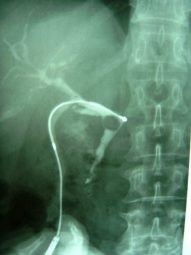

Litotripsia y extracción de cálculo de coledoco residual

Envíado por Dr. Carlos Miguel Zavaleta Consuegra